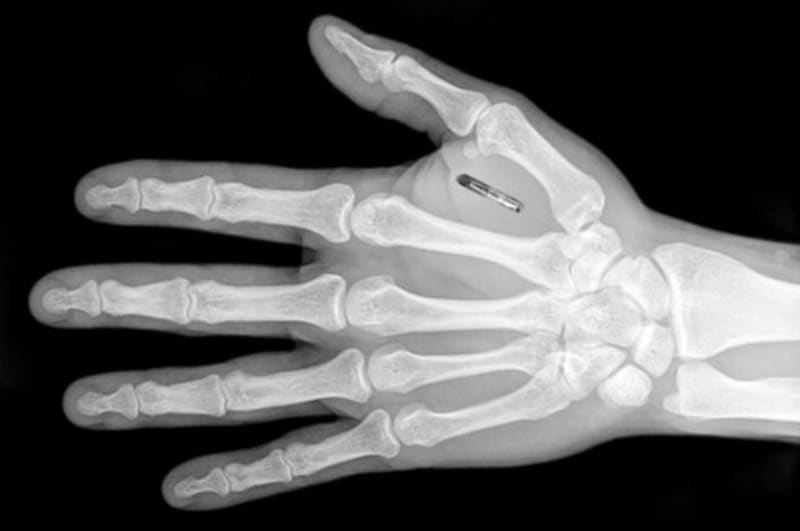

I think bio chips method is future secure money transfer. First of all I give a definition about the bio chip method. Bio chip method means, one small chip is inserted into the human body (most preferable hand palm) and control electronics equipment like mobile and ATM (for bank money transfer purposes) without using debit and credit cards.

WORKING: Different types of electronics equipment's (like mobile, ATM) needed programming code is uploaded to bio chip and then this chip is inserted in to human body and control via internet, NFC, wireless and Bluetooth technology. For bank money transfer purpose, candidate bank information will be programmed in to the bio chip after this chip is inserted in to human body.